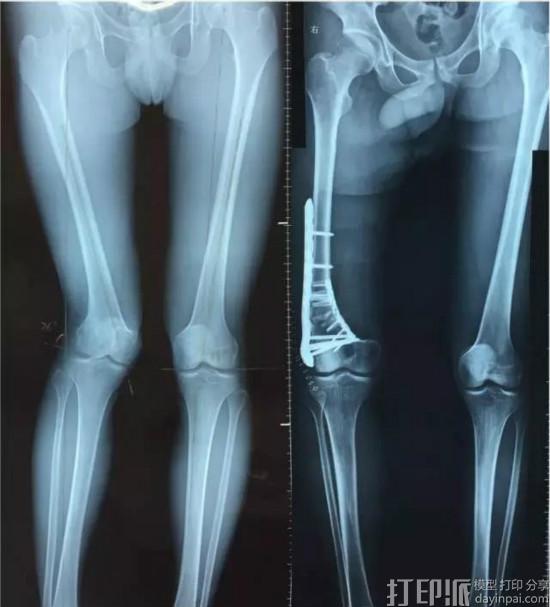

幼时骨折如今股骨严重畸形,3D打印让18岁小伙告别“鸭子步”

河南18岁的小伙晓华(化名)因为小时候骨折未处理好,导致股骨严重畸形,走路的样子像“鸭子步”。

2017年2月12日,晓华来到武汉协和骨科医院就诊。接诊的张波博士检查后表示,晓华的情况若不及时手术,可能会过早让他的关节报废,最后只能更换人工关节。16日,该院的叶树楠教授和张波博士联手为晓华实施手术。

由于晓华的股骨必须切掉一段,传统方法是术前计算出需要截骨的角度,术中用两根导针方向估计截骨角度再截骨,这样容易产生误差。为精确截骨,医生利用了3D 打印导航模板技术,术前打印出模型,定制精准角度的3D截骨导板,术前进行模拟操作,以便正式做手术时成竹在胸。

而制造这个3D打印导航模板的正是金玺银杏工业设计公司。手术第二天,医生便鼓励晓华下床活动。很快晓华已能拄着拐杖行走,这场手术让晓华彻底告别了“鸭子步”。张波博士说,如今3D打印技术在骨科中的应用越来越广泛,其优势在于让手术更加直观,而且大大提高了手术的精确程度,有利于患者术后快速恢复。